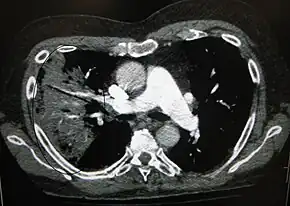

Cavitating pneumonia due to MRSA as seen on a CT scan

Bacteria are the most common cause of community-acquired pneumonia (CAP), with Streptococcus pneumoniae isolated in nearly 50% of cases.[34][35] Other commonly isolated bacteria include Haemophilus influenzae in 20%, Chlamydophila pneumoniae in 13%, and Mycoplasma pneumoniae in 3% of cases;[34] Staphylococcus aureus; Moraxella catarrhalis; and Legionella pneumophila.[18] A number of drug-resistant versions of the above infections are becoming more common, including drug-resistant Streptococcus pneumoniae (DRSP) and methicillin-resistant Staphylococcus aureus (MRSA).[21]

A black-and-white image shows the internal organs in cross-section as generated by CT. Where one would expect black on the left, one sees a whiter area with black sticks through it.

CT of the chest demonstrating right-side pneumonia (left side of the image)

A CT scan can give additional information in indeterminate cases.[34] CT scans can also provide more details in those with an unclear chest radiograph (for example occult pneumonia in chronic obstructive pulmonary disease) and is able to exclude pulmonary embolism and fungal pneumonia and detecting lung abscess in those who are not responding to treatments.[33] However, CT scan is more expensive, has a higher dose of radiation, and cannot be done at bedside.[33]